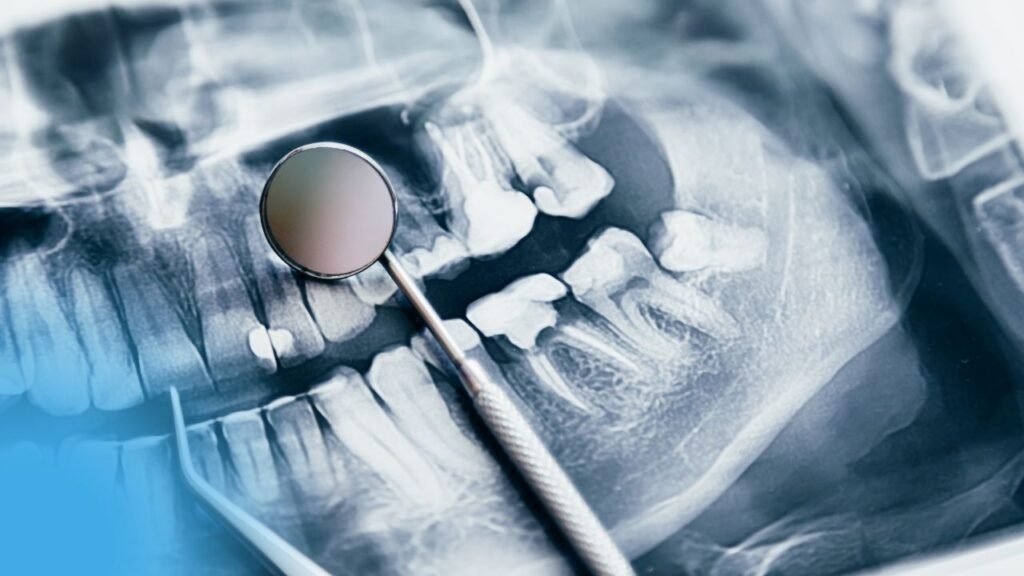

Lire l'articleTraitement des dents incluses Options de traitement Séquences de traitements A/ Premier temps orthodontique pré-chirurgical Souvent nécessaire pour augmenter et...